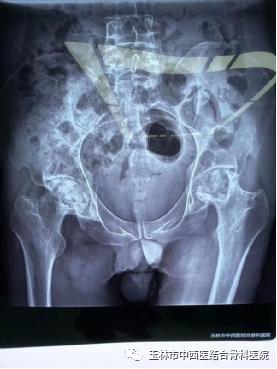

图三:术前

图四:术后

女性患者张某,44岁。经诊断为:左髋关节骨性关节病。这种疾病因为骨的退化、磨损,无特效药物治疗,目前手术治疗为最佳的治疗手段。由于该患者髋臼发育不良,髋关节挛缩,也就是说不同于正常的髋关节结构。手术是用人工的髋关节来代替现有关节,重新建立正常髋部结构,要求达20到30年乃至更久的使用寿命。如果手术中髋臼重建的位置、角度、深度任何一方面不精确,都将造成人工关节安装失败,进而影响它的使用寿命。手术难度大,技术要求高。微创髋关节置换(DAA)手术量超过1000多例的黎观保主任表示,仍然可以用微创手术技术来解决。

黎主任根据患者的病情,制定了独特的手术方案,就是在传统微创髋关节置换(DAA)技术基础上更进一步,使用anterior path技术,既比基尼切口(bikini incision)结合通道经髋前侧肌肉间隙做微创的髋关节置换。这与常规的手术相比,更容易做到小切口下充分显露髋臼和股骨侧,减少创伤,提高人工关节安装的精确度。手术时间约1小时,出血约100ml。患者术后第一天下地活动,自我感觉良好。